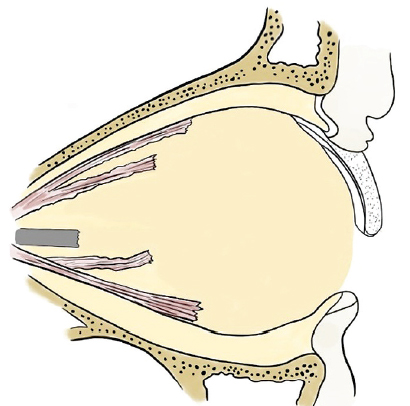

Fig. 3. Complete removal of the globe without simultaneous formation of a supporting-motor stump and without installation of an endoprosthesis. The remaining fragment of the optic nerve is present, contracted oculomotor muscles are visualized in the posterior section

Рис. 3. Полное удаление глазного яблока без одномоментного формирования ОДК и установки эндопротеза, оставшийся фрагмент зрительного нерва, в заднем отделе визуализируются сократившиеся глазодвигательные мышцы